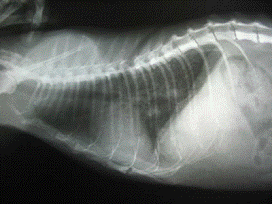

закрытия брюшной полости был сделан контрольный рентгеновский снимок грудной

клетки.(Рис. 6, 7)

Рис. 6, 7. Та же кошка после операции.